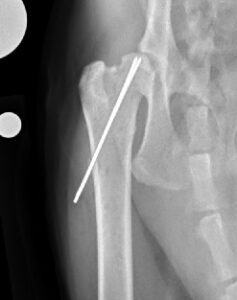

Fracture Repair with Pins or Screws:

Primary fracture repair, where the fracture is surgically put back together and secured in place using orthopedic implants (either pins or screws), can be performed in most cases by an ACVS board-certified veterinary surgeon (Figure 2).

In some cases of SCFE, due to chronicity of the fracture and/or the presence of unhealthy bone surrounding the fracture site, primary repair of these fractures may not be possible, recommended, or may be associated with a higher risk of complications.